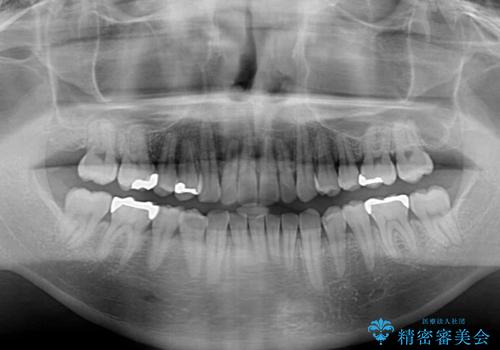

- 1年4ヶ月

下顎が左側にずれているため、上下正中は最大限合わせられるところまで合わせるゴールとなりました。